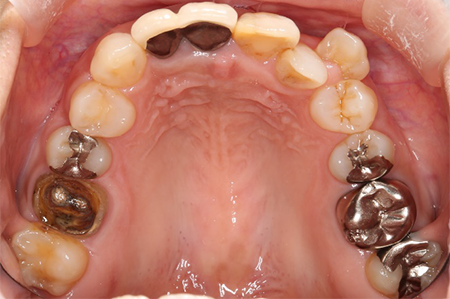

この患者様は長い事歯科医院には通っておらず、下の歯は前歯以外は全て崩壊していることが分かります。

前から見ても歯が欠けてしまい、歯茎も赤く腫れてしまっているのが分かります。

一般的には入れ歯が妥当かと思われますが、患者様は33歳、まだまだ人生は長いです。

奥歯がないと前歯でしか噛めなくなってしまい、残っている前歯もいずれダメになってしまいます。

また、奥歯がなくなってからの期間が長かったため、入れ歯が入るスペースが奥にないのが分かります。

様々なことを鑑み、患者様とも何度も話し合いを行い、下の奥歯には必要最低限のインプラントを、他の歯も外科処置を施しなるべく歯を抜かない方法を取りました。

最終的に抜歯した本数は下の歯5本。上の歯に関しては全て残すことが出来ました。

奥歯があることで前歯の負担を減らし、前歯を失うリスクを下げることが出来ます。